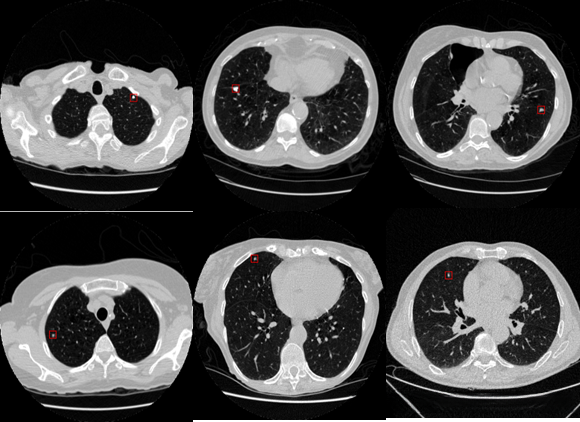

在本研究中,U-net模型输出的结果仅包含结节的位置坐标信息。通过OpenCV的cv2.rectangle()函数绘制了矩形框作为标注,便于直观观察。通过可视化技术,结果如图所示,其中孤立的实性结节和非实质性结节均能被精确检测出来,对医学临床诊断具有辅助参考价值。